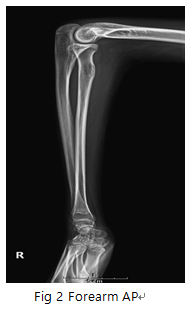

Forearm Lateral

- forearm의 fracture이나 fracture에 따르는 elbow joint과 Articulations of hand의 변위 등의 병변 유무를 관찰한다.

6) 영상 결과

① elbow 의 90“ 구부려야한다.

② Articulations of hand과 elbow joint이 포함되어야 한다.

③ radius, ulna distal부에서 일부 겹쳐야한다.

④ radial tuberosity는 전방을 향해야한다.

⑤ humerus의 both epicondyle는 겹쳐야한다.

⑥ radial head는 coronoid process와 겹쳐야한다.

- dislocation 주의, Carpal joint과 elbow joint 충분히 포함.